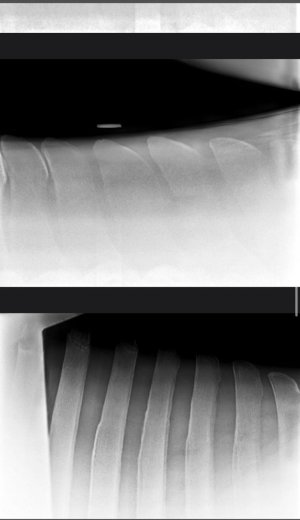

9 year old, 15.2 mare. She has been struggling with poor performance that has manifested in bucking, hollowness and reluctance to go forward. She started refusing fences which prompted a work up with her regular vet.

She was trotted up, lunged on hard and soft and had flexion tests. She was negative to all, with the exception of a very slight positive flexion on the hind limbs. Manipulation of the back was unremarkable.

Vets advised that x-rays revealed three very narrow interspinal spaces along the thoracic spine. These were medicated with a corticosteroid.

I would be interested to hear what others think of these radiographs and course of treatment? I feel like medicating is simply masking a problem that will still be present and symptoms will eventually return when the medication loses efficacy?